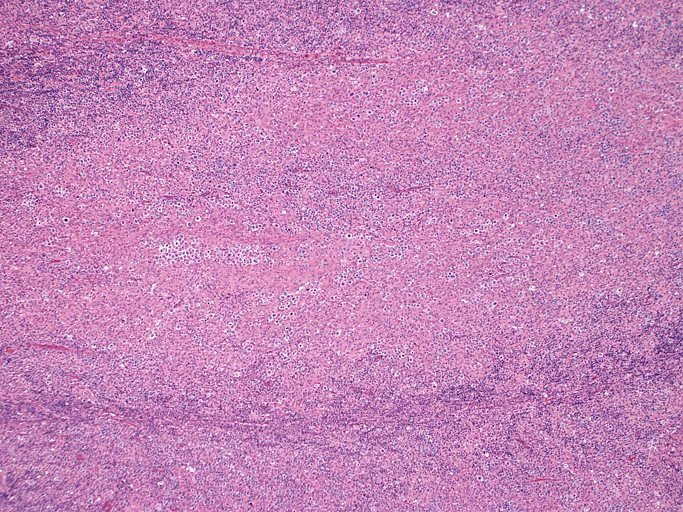

直径17mmの腫大したリンパ節。被膜は軽度線維性肥厚を示す。リンパ節の基本構造は失われ不明瞭な結節様構造が集蔟しているように見える。

結節構造内では, 好酸性細胞質をもつ組織球の増生を背景に大型異型細胞が散在性または集蔟して増殖している。被膜下にも線維化組織内にbizzarreな大型細胞が認められる。リンパ球は小型リンパ球が大型異型細胞を含む組織球性の結節辺縁に存在する。大型細胞は, centroblastic cellが多く, その他 Hodgkin cell-like cell, RS細胞様巨細胞, 腎臓型の核をもった細胞, 多型核の細胞など多彩な形態を示す。異型核分裂像をふくむ核分裂像が多い。